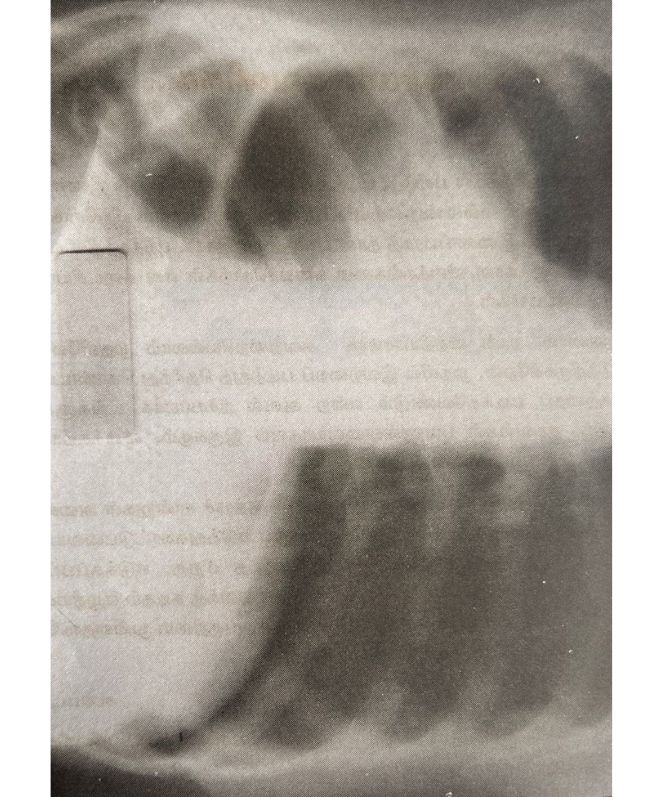

After - Lung Cancer 1

- Lung Cancer Scans – 1

Lung Cancer Scans 1

Before

After